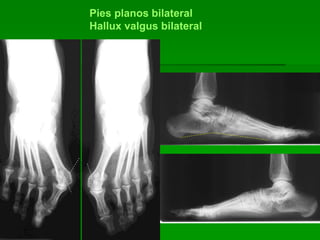

Pies planos bilateral

Hallux valgus bilateral

Línea de Schade alterada

(hundida a nivel escafoideo-cuneiforme)

Ángulo del arco externo, aumentado